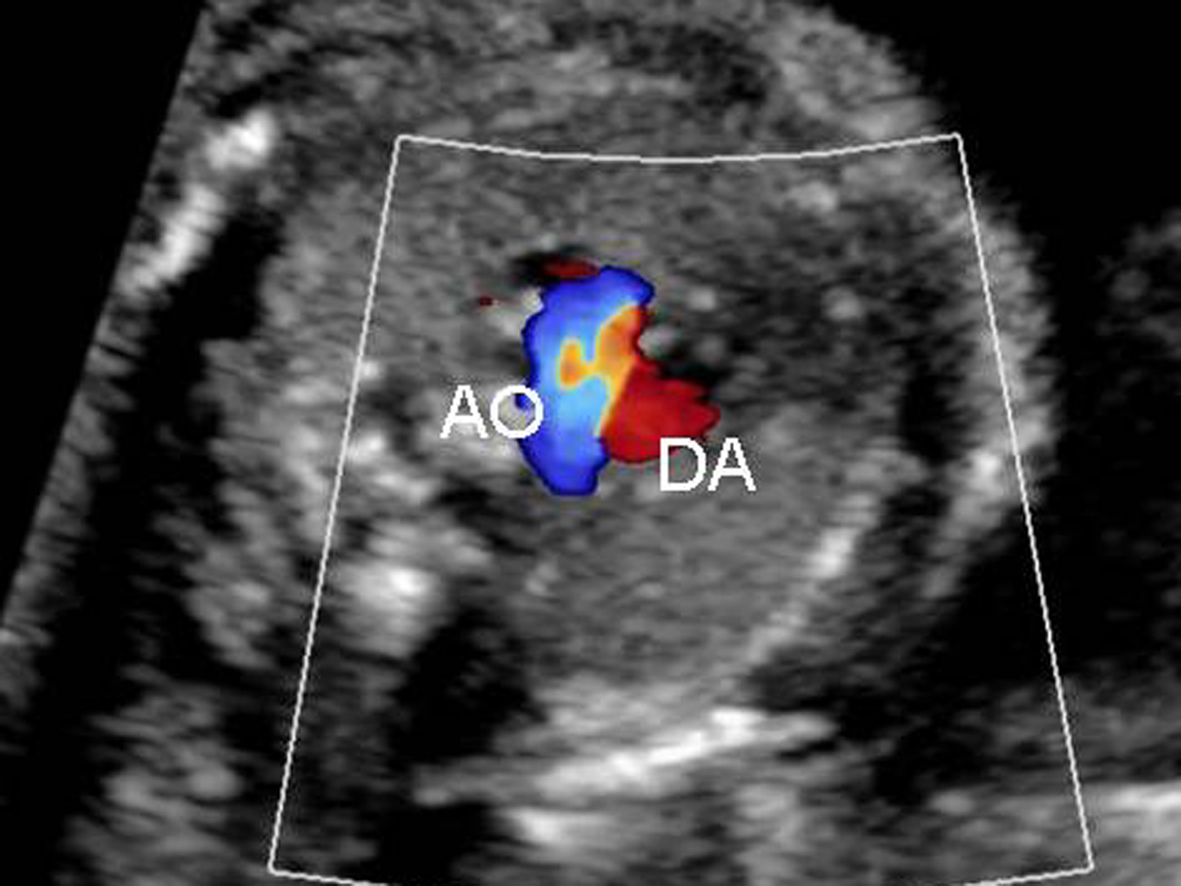

2. 超声诊断要点 二维超声显示左、右心室不对称,绝大多数右心室明显小于左心室(图3),少数也可正常大小或明显大于左心室;彩色多普勒超声检查三血管气管切面动脉导管与主动脉弓血流方向不一致,动脉导管内呈逆向血流(图4)。

图4 胎儿右心发育不良三血管气管切面动脉导管内呈逆向血流